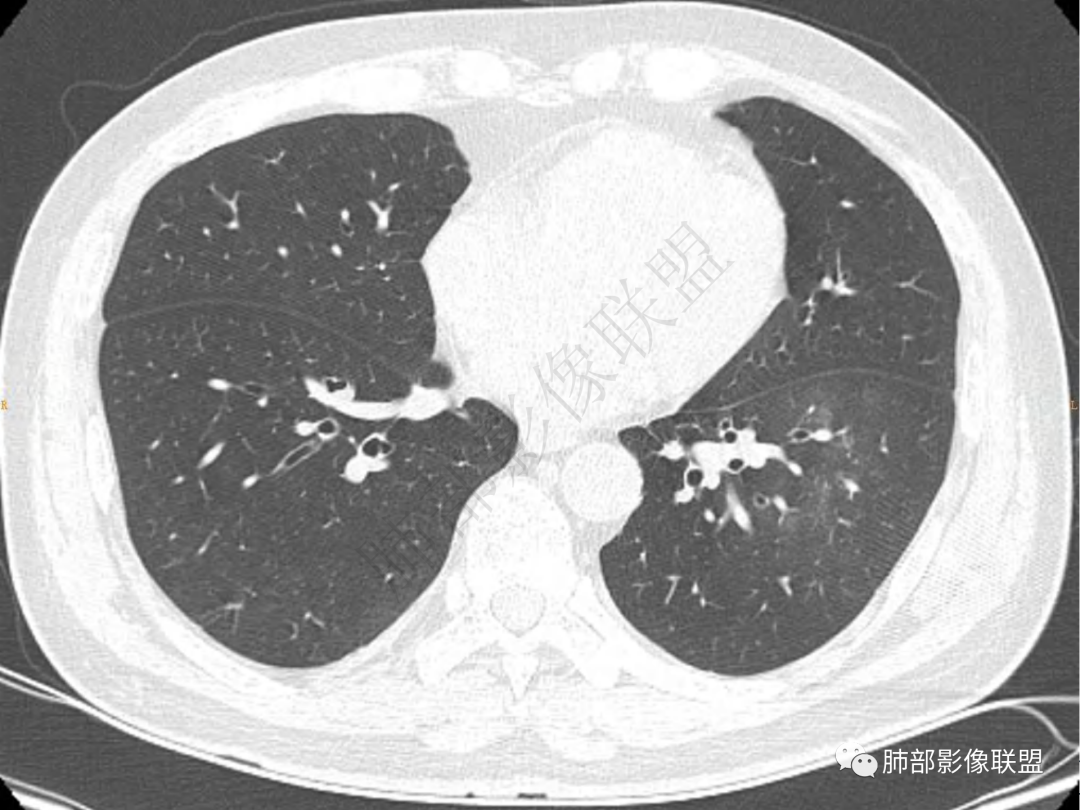

1.中年男性,咳嗽咳痰20余天,间断咯血2周

2.左肺下叶团片影,跨背段及内前基底段,实性部分类椭圆形,密度不甚均匀,可见毛刺及棘状突起,未见典型分叶及胸膜凹陷。病灶上下缘可见相应肺段支气管旁进侧出,管壁轻度增厚,未见狭窄阻塞。

3.周边较大范围磨玻璃影,边界相当模糊,小叶增厚明显。注意叶裂另一侧、左肺舌段亦可见磨玻璃影及增厚的小叶间隔。未见明确卫星病灶。

1.病灶不够密实,没有典型分叶,收缩乏力等,支气管未见截断等,缺乏一般肿瘤性肿块特征。

2.周围磨玻璃影边界不清缺乏限制,甚至“激惹”到相邻肺叶,也许提示较明显的炎性水肿。

正如多数老师分析到的,本例病灶炎性特点比较明显。